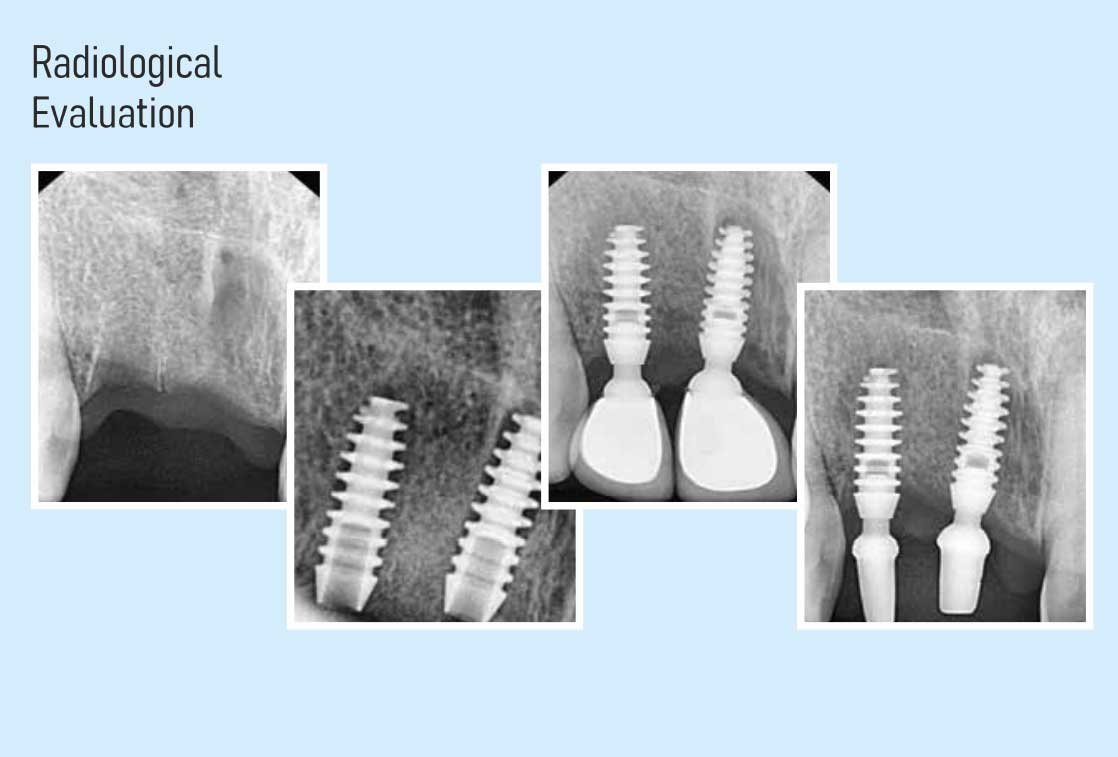

Two Stage Implants

The procedure is carried out in two stages spread over a mini- mum interval of 3 months. The first stage involves the placement of the implants and requires one to two sessions. The second stage involves the fabrication of the crowns (teeth). This is an obsolete technology and only used in those few cases where single stage implants are clinically not possible.

Single Stage Implants

The latest in dental implant technology, this involves comple- tion of the entire procedure, right from extractions, implant placements and fabrica- tion of the crowns (teeth) in one stage of approximately two weeks. This system can be used for almost all types and categories of cases.